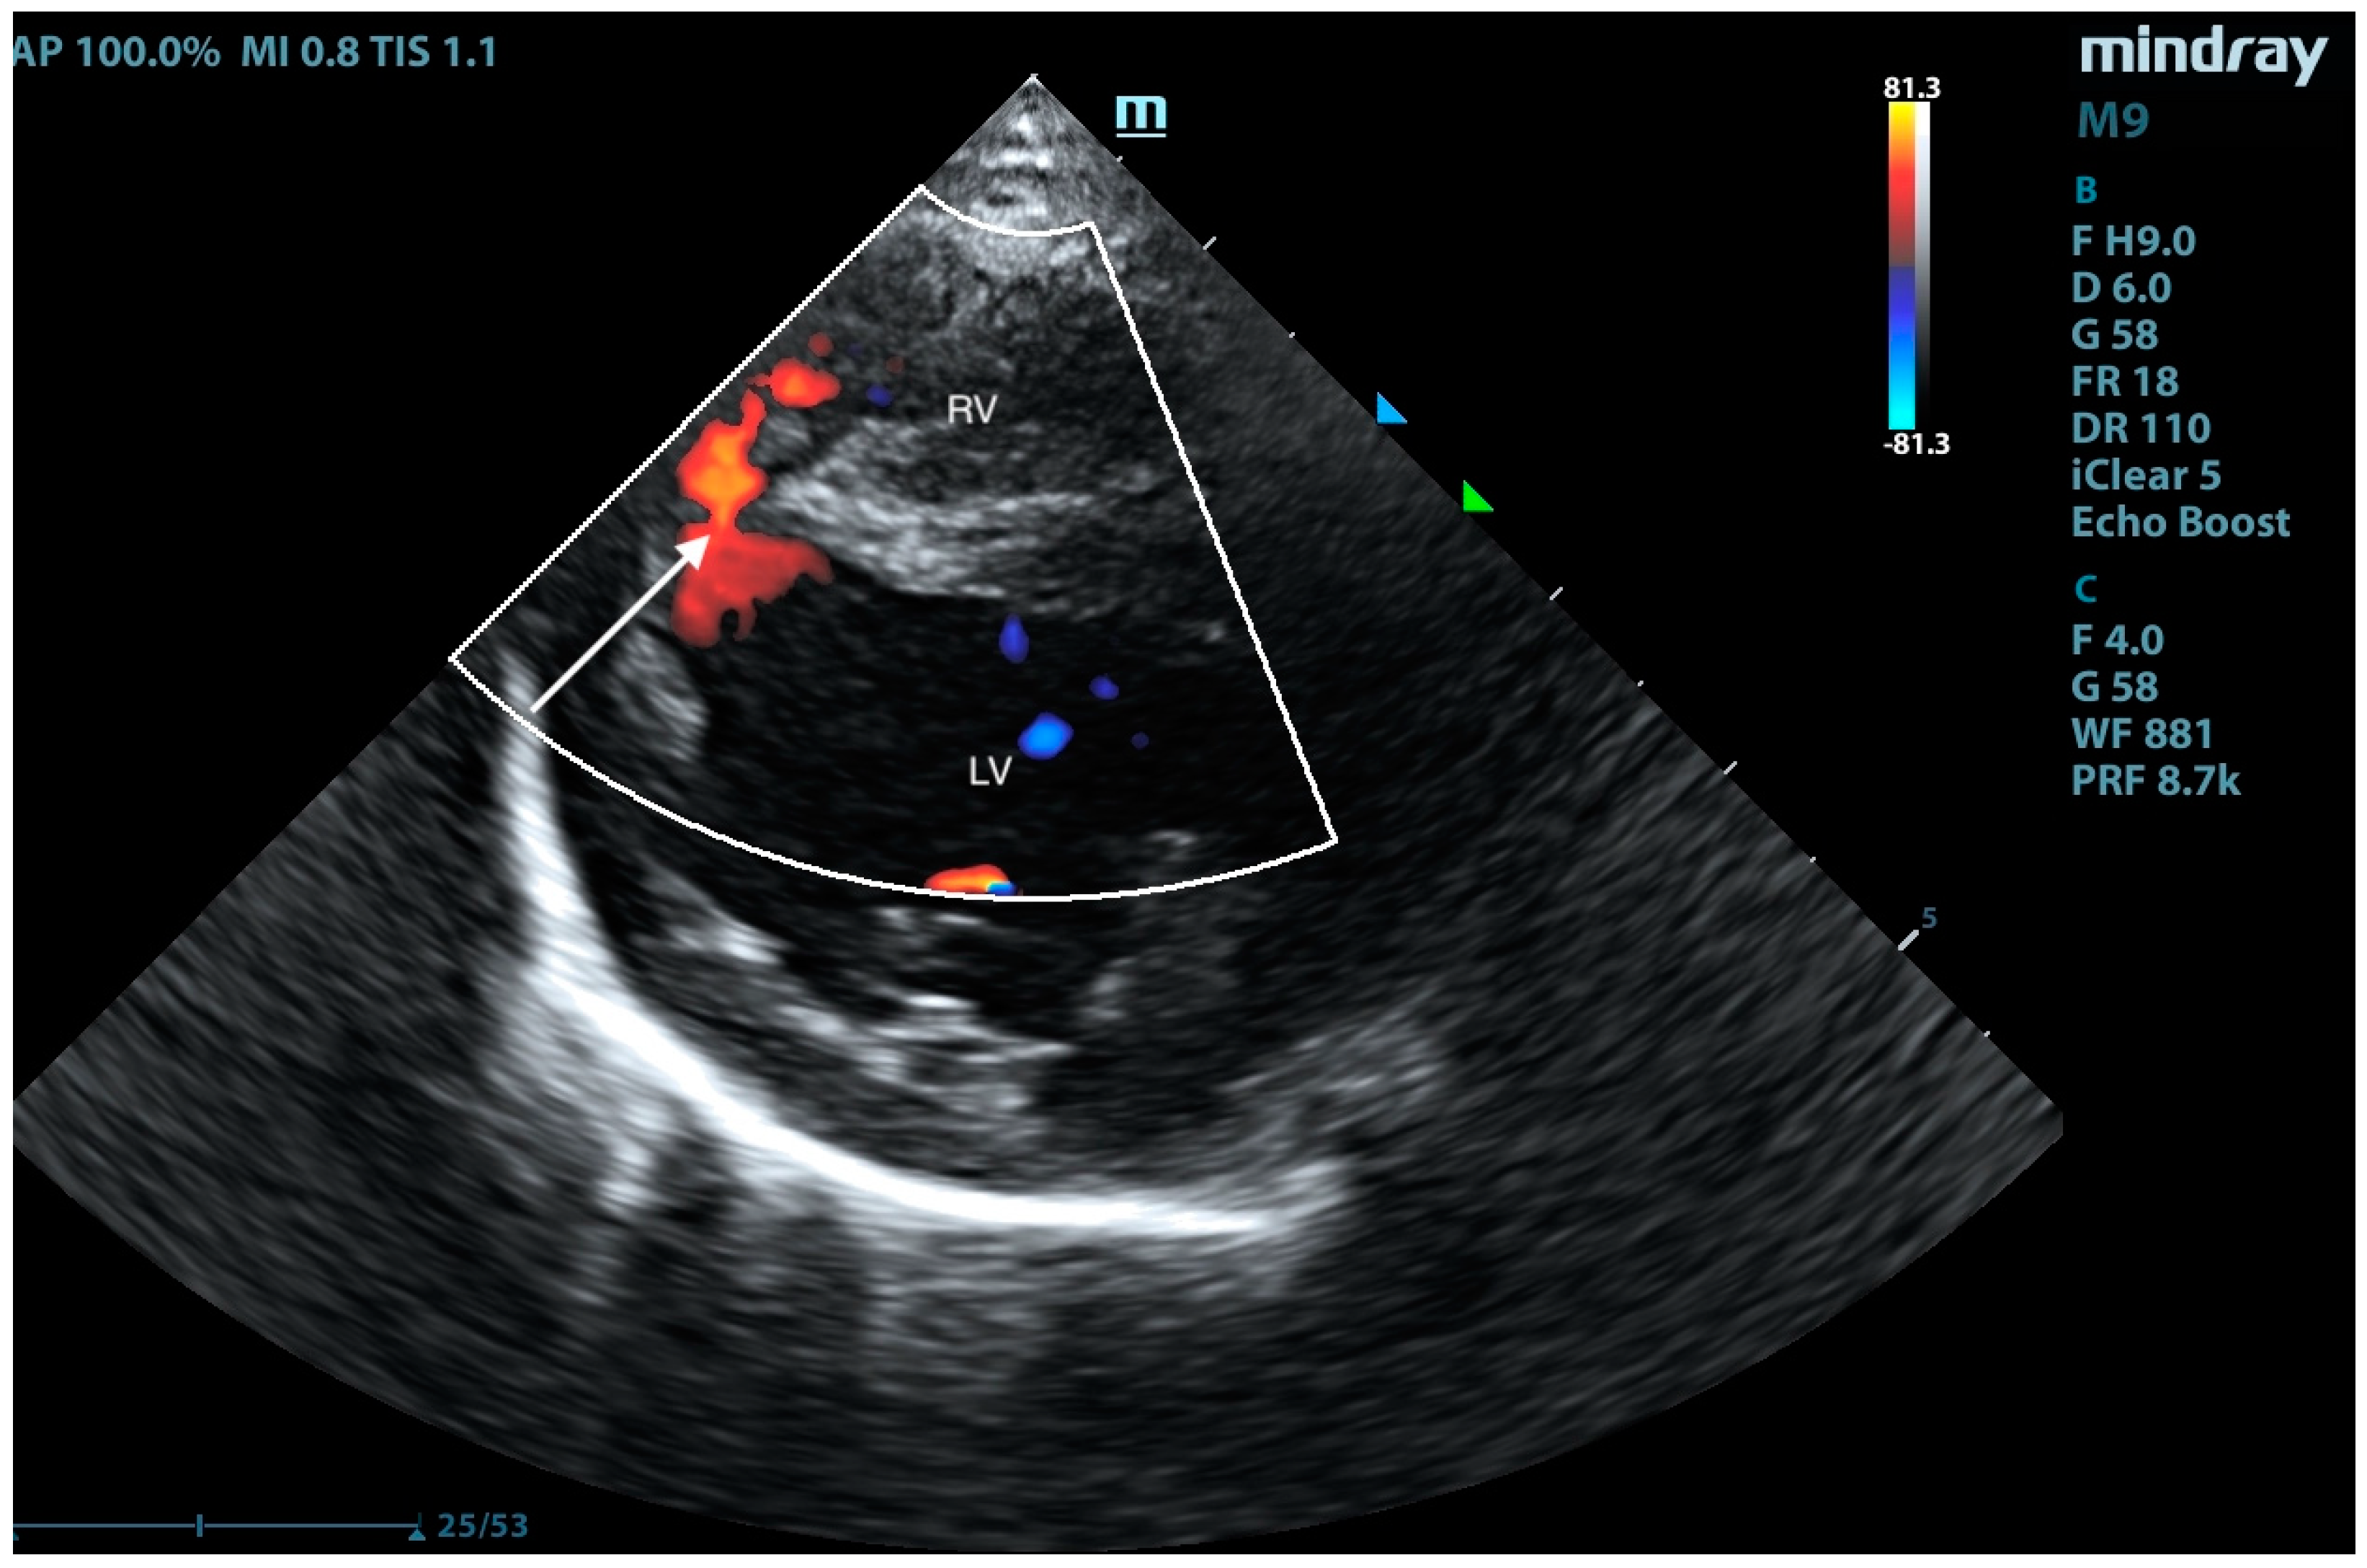

2. Case Presentation